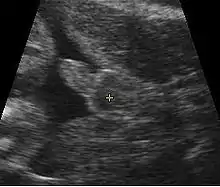

Ultrasonography image showing the fetus is a boy

Obstetric ultrasonography, either transvaginally or transabdominally, checks for various markers of fetal sex. It can be performed at or after week 12 of pregnancy. At this point, 34 of fetal sexes can be correctly determined, according to a 2001 study.[53] Accuracy for males is approximately 50% and for females almost 100%. When performed after week 13 of pregnancy, ultrasonography gives an accurate result in almost 100% of cases.[53]